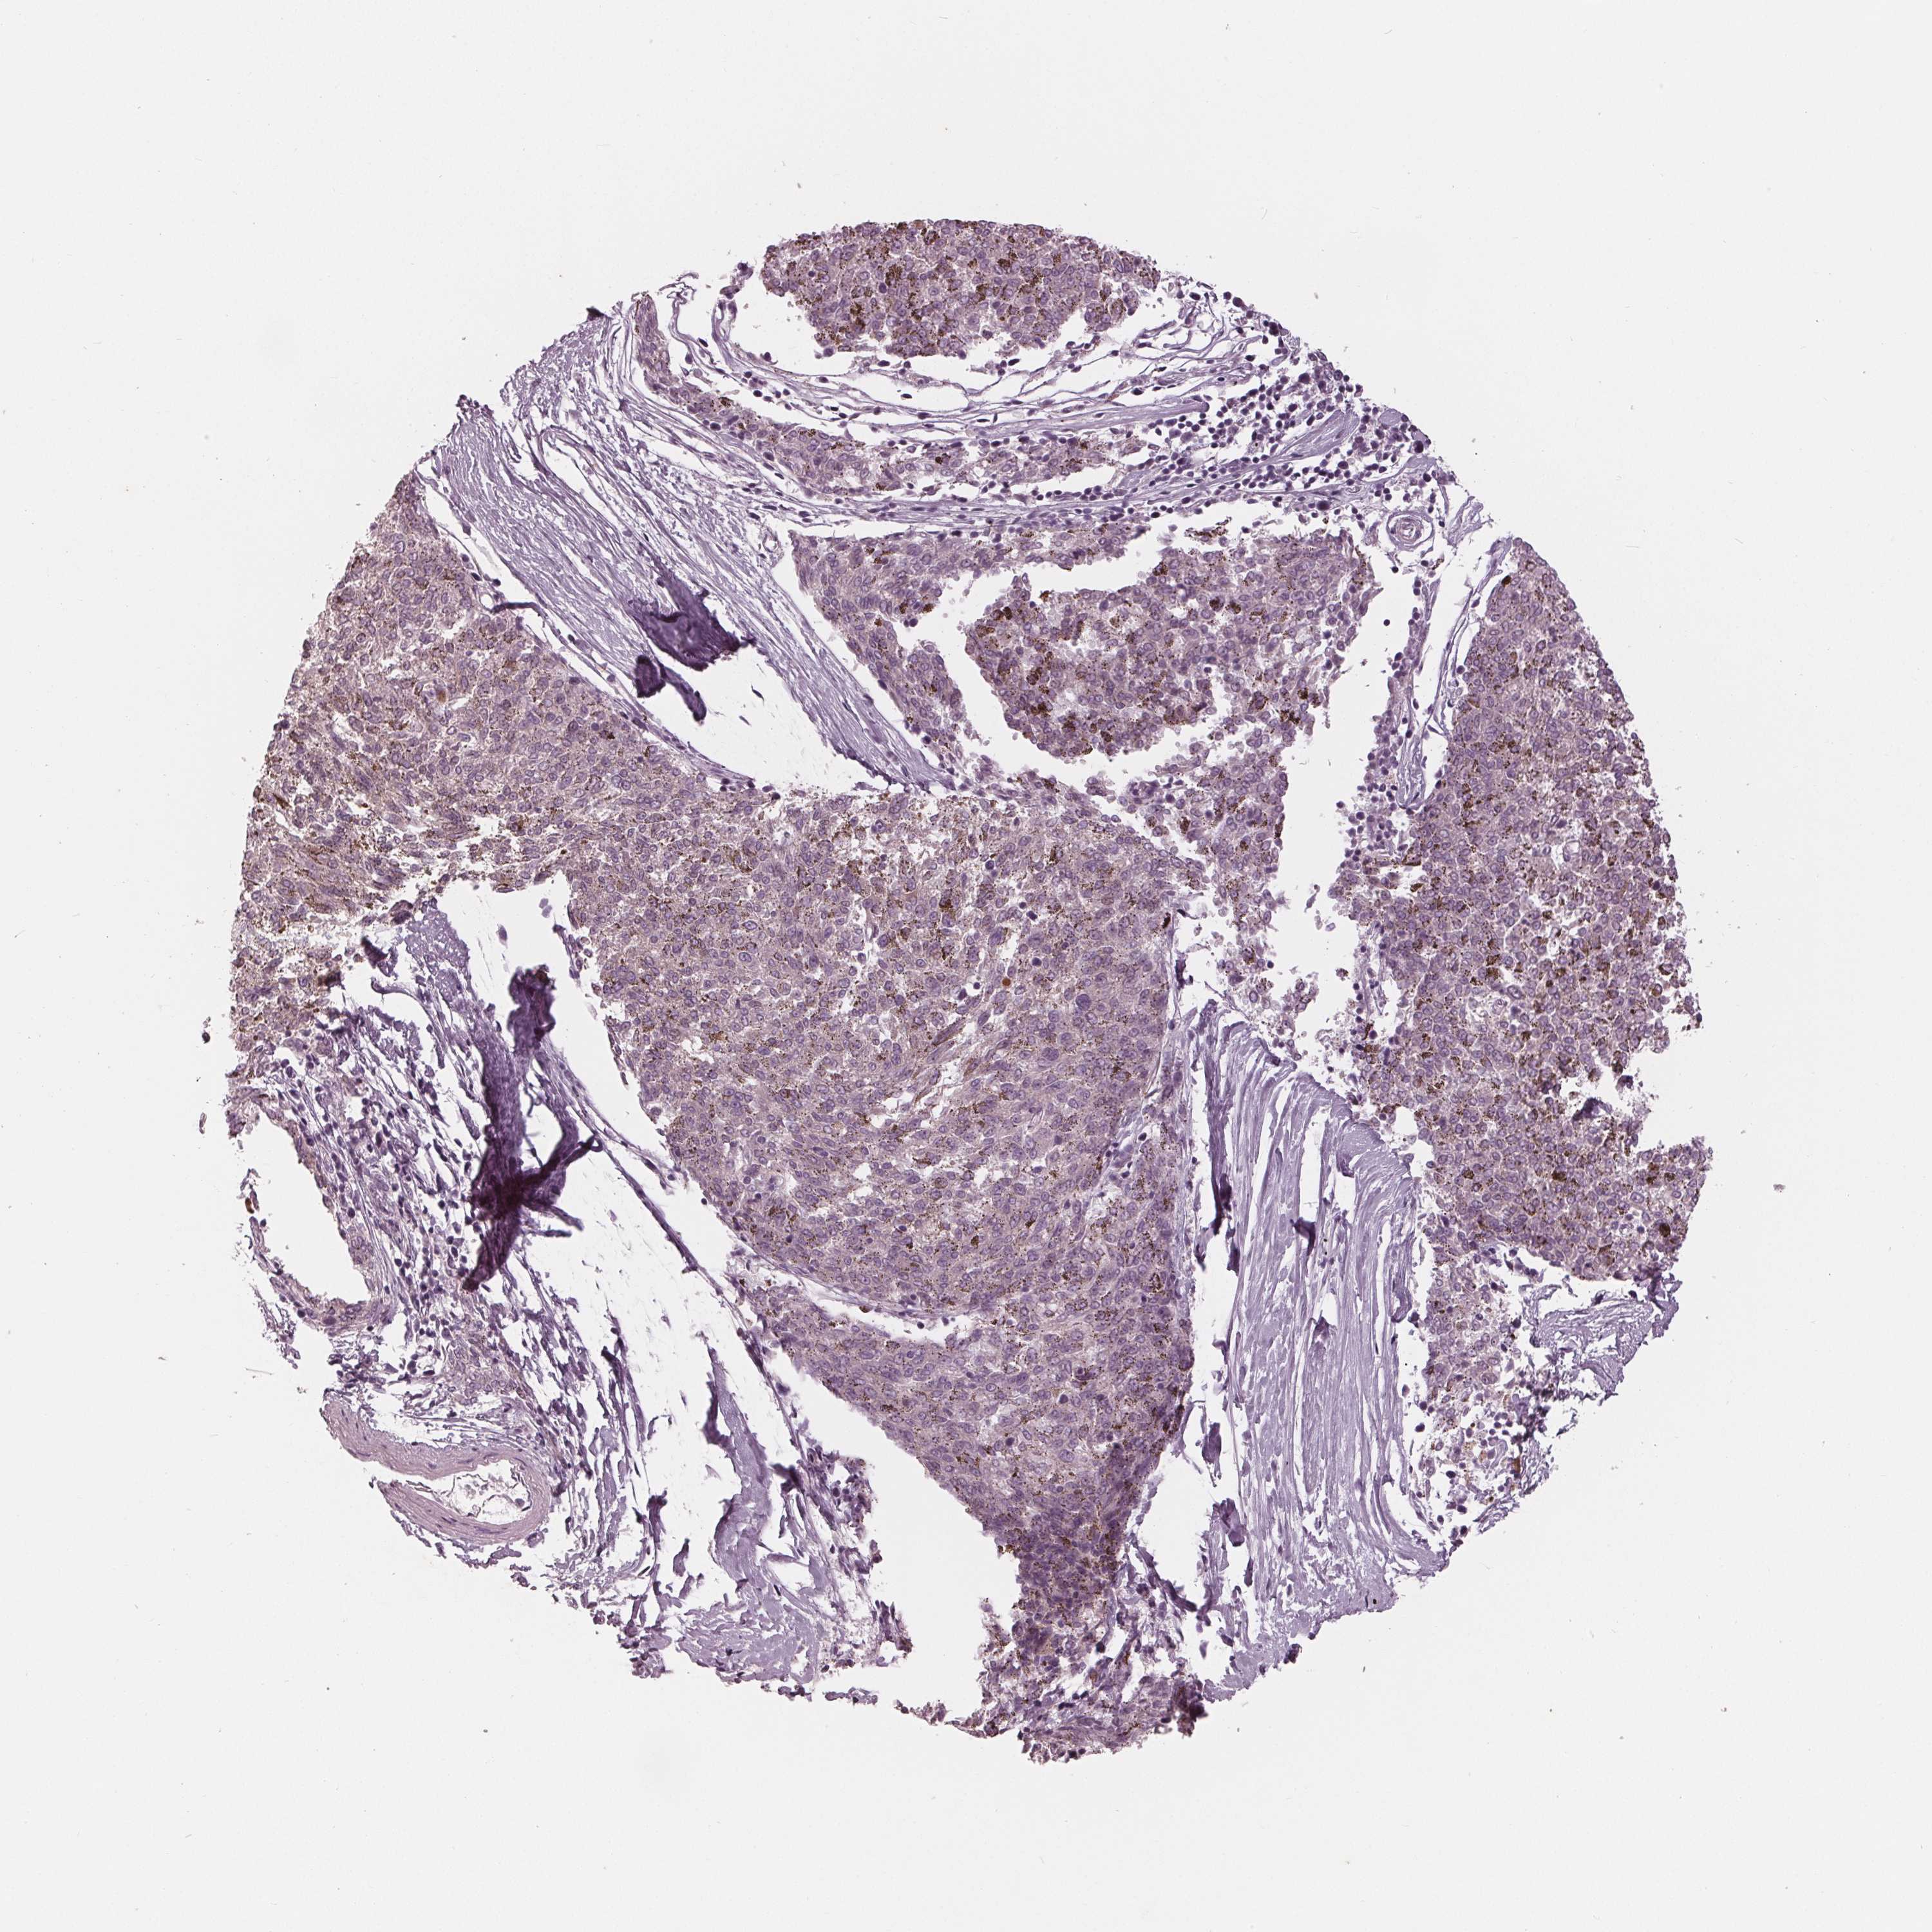

MELANOMA - Protein expressioni

A mouse-over function shows sample information and annotation data. Click on an image to view it in a full screen mode. Samples can be filtered based on level of antibody staining by selecting one or several of the following categories: high, medium, low and not detected. The assay and annotation is described here.

Note that samples used for immunohistochemistry by the Human Protein Atlas do not correspond to samples in the TCGA dataset.

Antibody stainingi

Antibody staining in the annotated cell types in the current human tissue is reported as not detected, low, medium, or high, based on conventional immunohistochemistry profiling in selected tissues. This score is based on the combination of the staining intensity and fraction of stained cells.

Each image is clickable and will lead to virtual microscopy that enables deeper exploration of all samples and also displays staining intensity scores, fraction scores and subcellular localization as well as patient and tissue information for each sample.

Antibody HPA066780

Staining

High

Medium

Low

Not detected

Intensity

Strong

Moderate

Weak

Negative

Quantity

>75%

75%-25%

<25%

None

Location

Nuclear

Cytoplasmic/membranous

Cytoplasmic/membranous,nuclear

Malignant melanoma, NOS

Malignant melanoma, Metastatic site